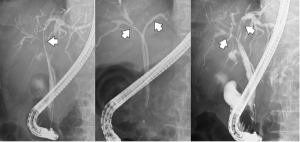

⚫︎ERCP

・総胆管結石(矢印)治療

内視鏡(胃カメラ)を使用し、胆管(肝臓の管)に詰まった石を除去します。

・小腸内視鏡での総胆管結石治療

胃の手術後などの場合、長い内視鏡(小腸内視鏡)を使い、胆管の治療を行います。

・胆道鏡での胆管結石治療

肝臓内の石・巨大な石には、胆道鏡(胆管用のカメラ)で石を割り(矢印)除去します。

・胆管閉塞に対する内視鏡治療

膵がん・胆管がんでは、胆管が詰まり「黄疸」が出ることがあります。内視鏡で「プラスチック・金属のチューブ」を胆管に入れ、詰まりを解除します。

・胆管閉塞への内視鏡治療

肝臓内の胆管が詰まった場合、内視鏡で「プラスチック・金属のチューブ」を複数本留置します。